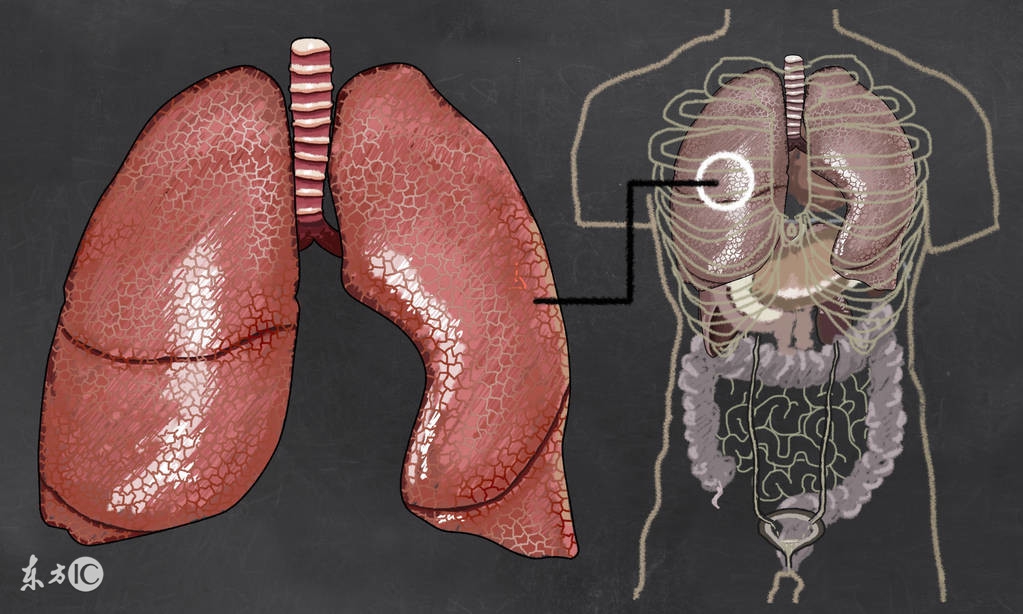

不少中老年人,不仅因此过早地丧失劳动能力,长期咳喘,痛苦万分,而且往往对病症悲观失望,有的甚至对人生丧失信心。其实,患有肺气肿的病人,如能进行合理运动,可以收到改善症状的明显效果。

老年人肺气肿怎么治